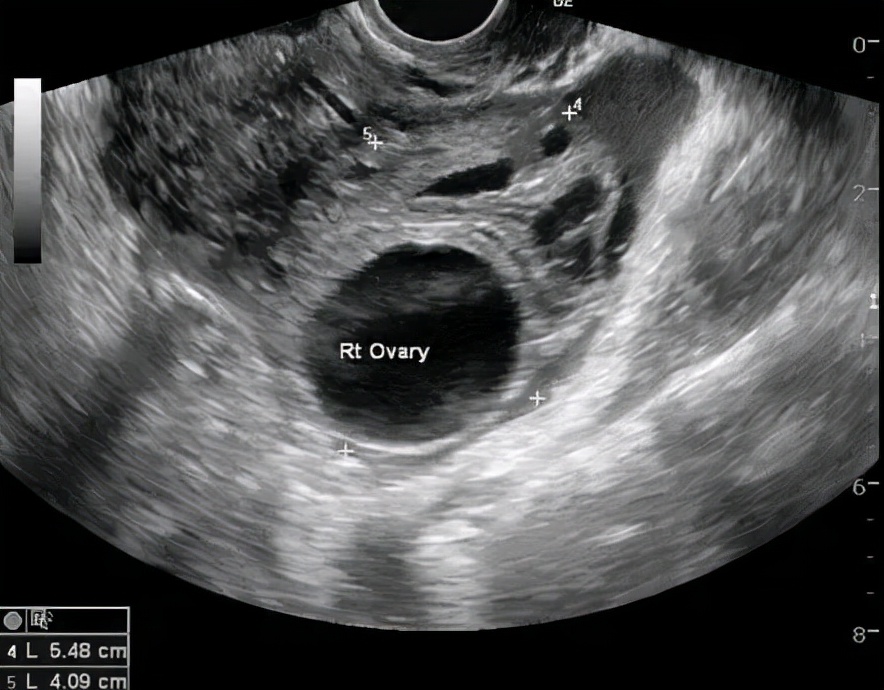

上面我们提到,卵泡破裂排卵之后,就成为了黄体,而黄体囊肿是指在卵泡破裂的同时,破裂口的小血管同时发生破裂,这时血液潴留在黄体腔里就形成了血肿。直径一般为4cm,黄体血肿被吸收后,会形成黄体囊肿。若黄体血肿发生破裂,会引起起腹痛等不适,个别出血多的可能会导致失血性休克,和宫外孕相似,也不容忽视。

黄体血肿特点: 囊内回声不均匀,有多种表现,比如杂乱回声、网状结构、实性稍高回声,甚至有密集的光点样强回声。一般会自然消退,同样建议1-3个月后月经干净3天左右复查。